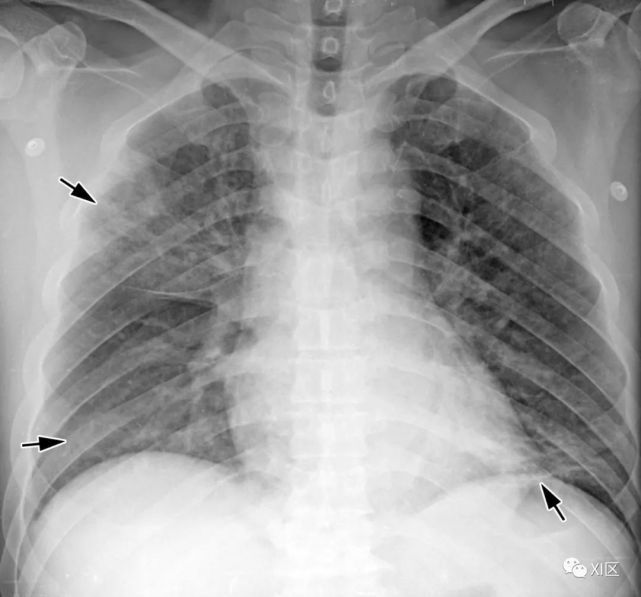

图11 28岁男性白血病患者骨髓移植后移植物抗宿主疾病,诊断为CMV病毒性肺炎。

(上) 最初的胸片显示两肺弥漫性GGO(箭头)。在同一天,在较低的气管水平(中)和叶间区水平(下)上获得的轴位薄层(1mm)CT图像显示两个不明确的GGO结节、小叶间隔增厚(箭头)和弥漫性GGO(箭),双侧胸腔积液(下图中)的数量较少。

Koo H J , Lim S , Choe J , et al. Radiographic and CT Features of Viral Pneumonia[J]. Radiographics, 2018, 38(3):719-739.